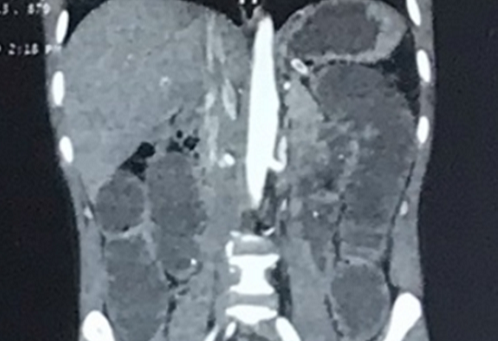

Hình ảnh phim chụp đoạn ruột bị tắc của bệnh nhân - Ảnh: VTC News |

Bệnh viện Đa khoa tỉnh Tuyên Quang vừa cấp cứu bệnh nhân T.T.N., trú tại Tuyên Quang nuốt phải xương cá. Trước đó một tuần, người này bị hành hạ bởi những cơn đau bụng âm ỉ, bí trung tiện và đại tiện.

Qua thăm khám và làm các xét nghiệm, bác sĩ chẩn đoán bệnh nhân bị tắc ruột hoàn toàn, phải phẫu thuật cấp cứu gấp để bảo toàn tính mạng.

Quá trình mổ kiểm tra thấy ruột non của bệnh nhân bị dãn to, có khối bã thức ăn dài khoảng 15cm, có nhiều xương cá nhỏ găm từ giữa ruột vào thành ruột, gây tắc hoàn toàn lòng ruột.

Để xử lý, các bác sĩ mở thành ruột lấy hết bã thức ăn, khâu đóng thành ruột và ổ bụng. Hiện tại, sau mổ 1 ngày, bệnh nhân ổn định, tiếp tục được điều trị tại khoa Ngoại Tổng hợp của bệnh viện.